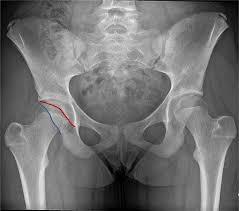

고관절 통증이 나타나는 위치

고관절 통증은 엉덩이 깊숙한 부위에서만 느껴진다고 생각하기 쉽지만, 실제로는 다양한 위치로 퍼져 나타날 수 있습니다.

• 사타구니 안쪽 통증

특히 사타구니 통증은 고관절 이상을 가장 강하게 의심할 수 있는 신호로 전문가들도 중요하게 보는 증상입니다.